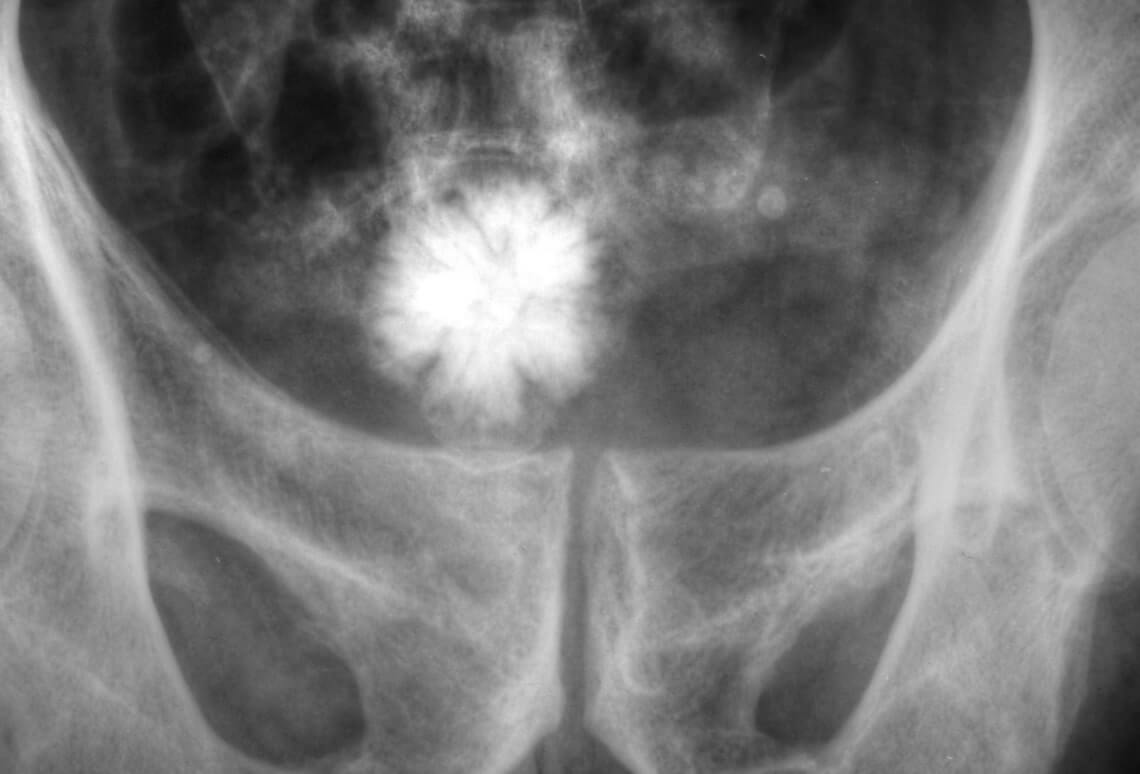

Gall bladder stones or Cholelithiasis (gallstones) are hardened deposits of digestive fluids (stones or lumps) that form in the gallbladder or bile duct.

Gallbladder contains chemicals such as cholesterol, calcium bilirubinate, and calcium carbonate, which solidifies into either one large stone or several small ones. Gallstones can vary in their size from as small as a sand grain to as big as a golf ball. Theses stones can develop into single large gallstone, hundreds of tiny stones, or both small and large stones. Gallbladder attack or Biliary Colic: Gallstones causes sudden pain in the upper right abdomen which occurs when gallstones block the ducts of the biliary tract. This sudden pain is called as gallbladder attack or biliary colic.